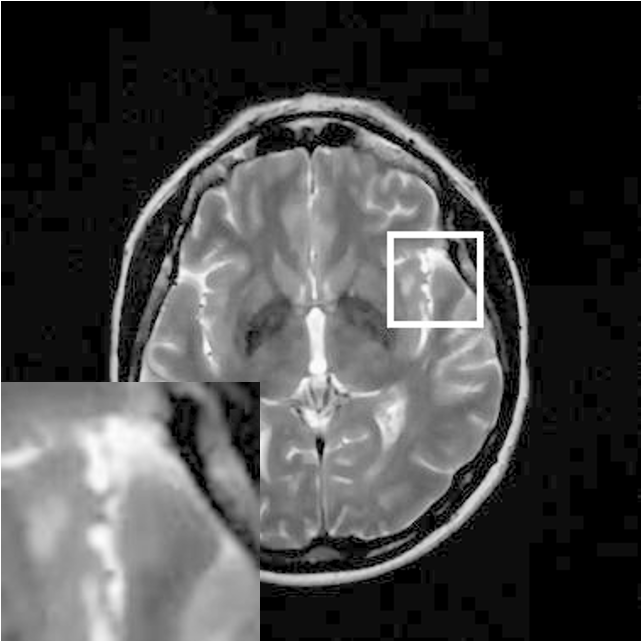

Figure 9: Reconstruction results for 30% radial sampling. (a) Original. (b)-(h) Reconstructed images. (i)-(n) The errors of six CSMRI methods.

As shown in Figs. 7, 8 and 9, Sparse MRI and DLMRI have a lot of unpleasant artifacts, Residual learning and U-net can eliminate most of artifacts, but are not ideal for restoring image details. However, the proposed method can reconstruct better MR images, which outperforms other competitive methods in visualization of structures reconstruction and artifacts removal. Meanwhile, we can see from the absolute error residuals for three sampling experiments that the proposed MDN algorithm restores a finer detail structure than other algorithms. Moreover, we present the PSNR and SSIM values in Table I for different algorithms, sampling masks and sampling rates. It is demonstrated that the proposed method provides better reconstruction performance and visual results than other competitive methods. We can also see the obvious improvement of all algorithms over zero-filling both in visualization. In particular, a higher SSIM value of Sparse MRI appears when using 30% variable density random sampling, however, Sparse MRI generates more artifacts than the proposed MDN.